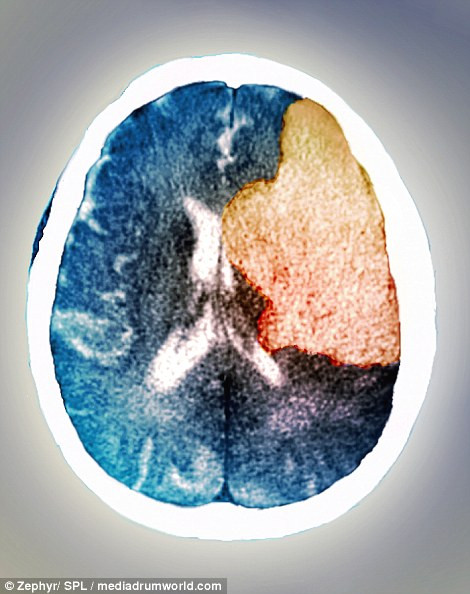

Đây là hình ảnh của não trong cơn đột quỵ. Ảnh chụp CT cho thấy vùng não bên phải của bệnh nhân đã bị liệt sau khi bị đột quỵ. Đột quỵ xảy ra khi lượng máu cung cấp cho một vùng não nào đó bị thiếu hoặc hoàn toàn không có khiến các tế bào não chết đi.